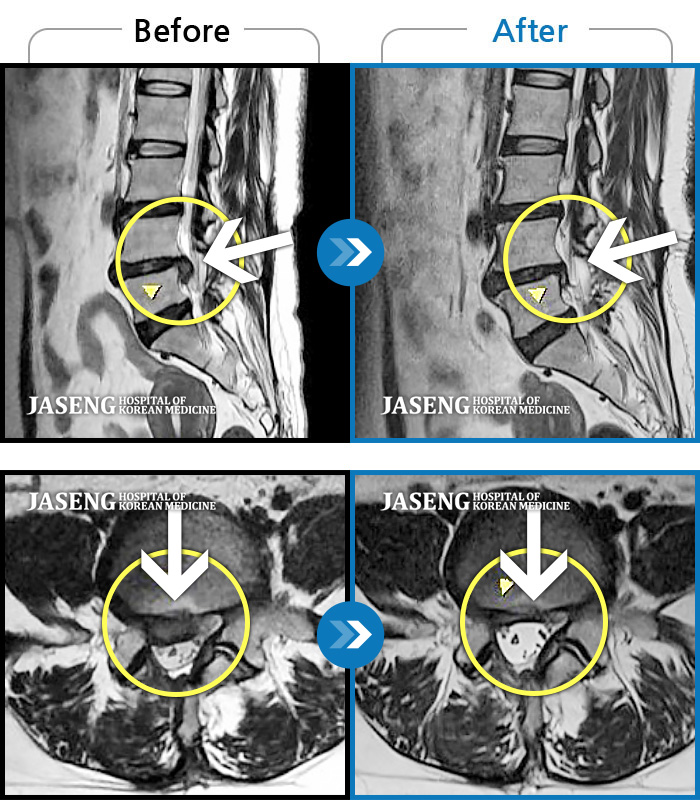

허리에 갑작스럽게 고통스러운 통증으로 내원해서 디스크라는 병명에 놀랐고 무서웠는데 따뜻하고 친절한 진료로 일단 마음이 안정이 되었고 무엇보다 수술없이도 치료가능 할꺼라는 말씀에 위안이 되면서 이선생님만 믿고 치료를 받으면 난 살겠다 라는 마음을 갖게 되며 입원치료를 받기 시작합니다. 침맞는 두려웅, 허리통증으로 유별나게 겁이 많은 나였지만 불편한내색 한번 없이 치료를 해주시고 안정을 주시니 말을 안해도 느껴지는 따뜻한 의료진이 내 주치의인게 너무 감사할따름이였습니다. 하루하루 치료과정에 상태도 꼼꼼히 체크해주시고 정말 거즘 기여서 병원을 들어와서 두발로 씩씩하게 퇴원을 하게 도와주신 장영우원장님 진심으로 감사드리고 자생한방병원에 따뜻한 의료진이 있어 안심이 됩니다

우리 원장님은 언제나 친절하고 반갑게 맞아주셔서 너무 너무 좋습니다.허리가 많이 아팧었는데 워낭님 덕분에 하루하루가 좋아지고 있습니다. 스스로 느끼기에도 아주 많이 편안해졌습니다. 이대로리면 금방 나을것 같습니다. 마음으로 늘 감사드리면서 우리 원장님 굉장히 많이 많이 칭찬하고 싶습니다. 우리 장영우 원장님 사랑합니다~^^

다리저림과 허리통증으로 장원장님께 치료 후 몸이 회복되어 감사 인사드립니다. 짧은 기간이었지만 원장님께 받은 추나치료는 정말 환자인 제가 받으면서도 치료하시는 원장님 손을 걱정할 정도로 매 번 정성스럽게 해주셨어요. 지인들에게 원장님 자랑을 해서 치료받은 후 모두 한결같이 정말 최고!!!라는 찬사 를 합니다. 아마도 열정적인 침!치료 덕분에 빠른 효과가 있지 않았나 생각합니다~~^^ 성실하시며 환자를 정말 아끼시는 마음에 감탄 하였고 진료할때면 원장님의 배려하시는 모습에 매 번 감동을 하였습니다. 광주자생에서 환자에게 가장 편안하고 즐거운 진료시간이 되도록 해 주시는 장 영우원장님!!! 진심으로 감사드립니다. 늘 건강하시고 건승하세요~^*^

살짝만 움직여도 허리가 끔벅거리고 아프고 일어나거나 눕지도 잘 못하고 걸음도 제대로 못걷고 옷도 못입을정도로 통증에 시달렸읍니다. 입원첫날 원장님한테 침맞고 통증이 좀 가라앉았어요 MRI 찍어보니 왼쪽디스크는 터졌고 6번은 터지기 직전 3 4 번은 부어있고 12번 1번은 심각한상태구요 몇일 통증치료하며 끔벅거리는게 없어 살겠더군요 종아리 발바닥 발등이 저려 무척힘들었는데 치료받으며 저린것도 허리아픈것도 많이 좋아졌어요 자금은 걷는것도 훨씬가벼워 졌어요 40대 후반 나이로 내가 벌써 이렇게 몸을 못쓸정도로 아프나 싶어 암담했었는데.. 치료받으며 좋아지니 마음도 훨씬 가볍네요 늘 친절한 모습으로 그날그날 상태를 살펴보며 정성껏 치료해 주시는 원장님 넘~~ 감사합니다!! 우리 원장님??????